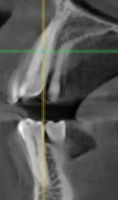

При анализе и описании компьютерной конусно-лучевой томографии (рис. 2а-г) была выявлена генерализованная первичная дегисценция вестибулярной пластинки кости от 1/2 до 3/4 длины корней зубов, зубной ряд целостный, все зубы витальны, кариозных поражений нет. Тип кости 1-2 (Lechkolm и Zarb, 1983), первичная дегисценция вестибулярной костной пластинки превышает пределы возрастной атрофии.

10. Анализ компьютерного томографического обследования

Через 12 месяцев (рис. 7а-г) на срезах компьютерной томограммы 11-ый и 13-ый зубы находятся в костной ткани, при этом костные пики и перегородки укрепились, объем их увеличился; вестибулярно заметен объем костной массы, предположительно компактной формации, исходя из электронной плотности участка. Этим объясняется отсутствие рецидива при лечении рецессии десны как в случае применения аутотрансплантата, также и ТМО (dura mater).